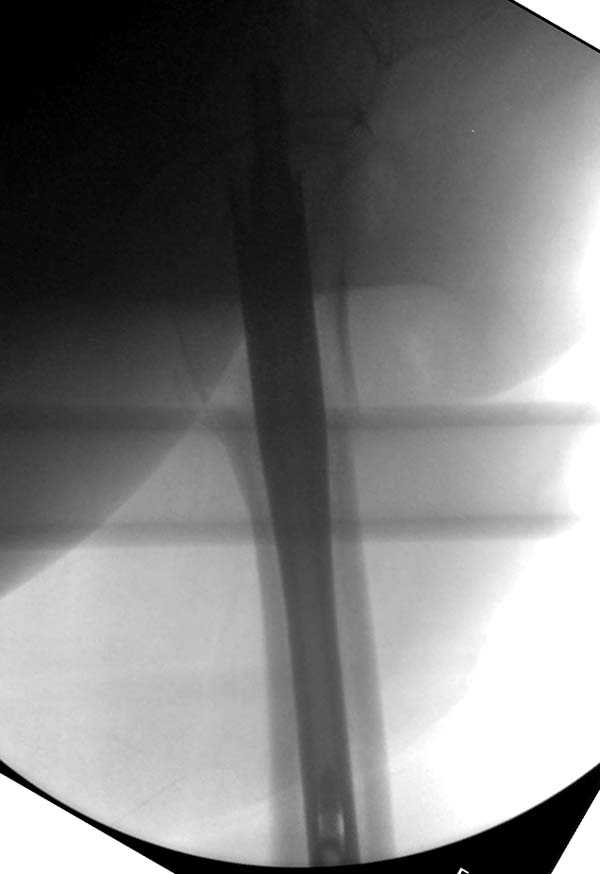

Здесь представлен случай, где в послеоперационном периоде обнаружена техническая ошибка, Gamma 3 установлен с нарушением методики. Больная в 91 лет, прооперирована через день после поступления и выписана через 48 часов.

При первом послеоперационном поликлиническом осмотре больная предъявила жалобы на боли в бедре. В серийных снимках обнаружен продольный перелом верхнего отдела бедра.

Считаем, что техническая ошибка произошла во время установки гвоздя, когда рассверливанию канала не уделили должного внимания. Канал остался узковат, и гвоздь был забит с силой. Полная нагрузка конечности приостановлена на две недели, и боли в конечности изчезли. Больная начала нагрузку и перелом срастается. -- Djoldas Kuldjanov, M.D. Associate Professor Department of Orthopedic Surgery St. Louis University